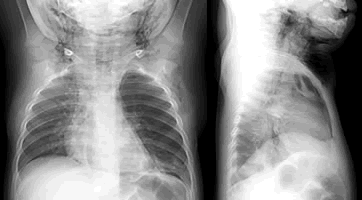

患儿,男,15个月。主因咳嗽5天,发热2天,发现颈前肿胀半天就诊。查体:精神差,呼吸促,左肺呼吸音低。颌下、颈前部、前上胸部和左腋下肿胀,有握雪感。X线胸片(图1)显示:右肺及左下肺纹理增多、模糊,左肺野透光度增强,左下肺近膈面处可见斑片状、片絮状高或略高密度影,边缘模糊。心影纵隔略右移,纵隔边缘及纵隔内可见线状透亮影(■)、横膈连续显示(■)。颌下、颈前、前上胸部及左腋下见多发不规则蜂窝状透亮区(图2 )。胸部透视:与胸片相仿,但未见明显纵隔摆动或心影反常大小。X线诊断:纵隔积气,颌下、颈前、前上胸部及左腋下皮下积气;左肺气肿,左下肺实质浸润;左主支气管异物可能性大。

患儿于全麻下接受纤维支气管镜检查,于左支气管开口处见一白色异物影,分次取出,异物为花生米,约1/4粒大小。, 百拇医药